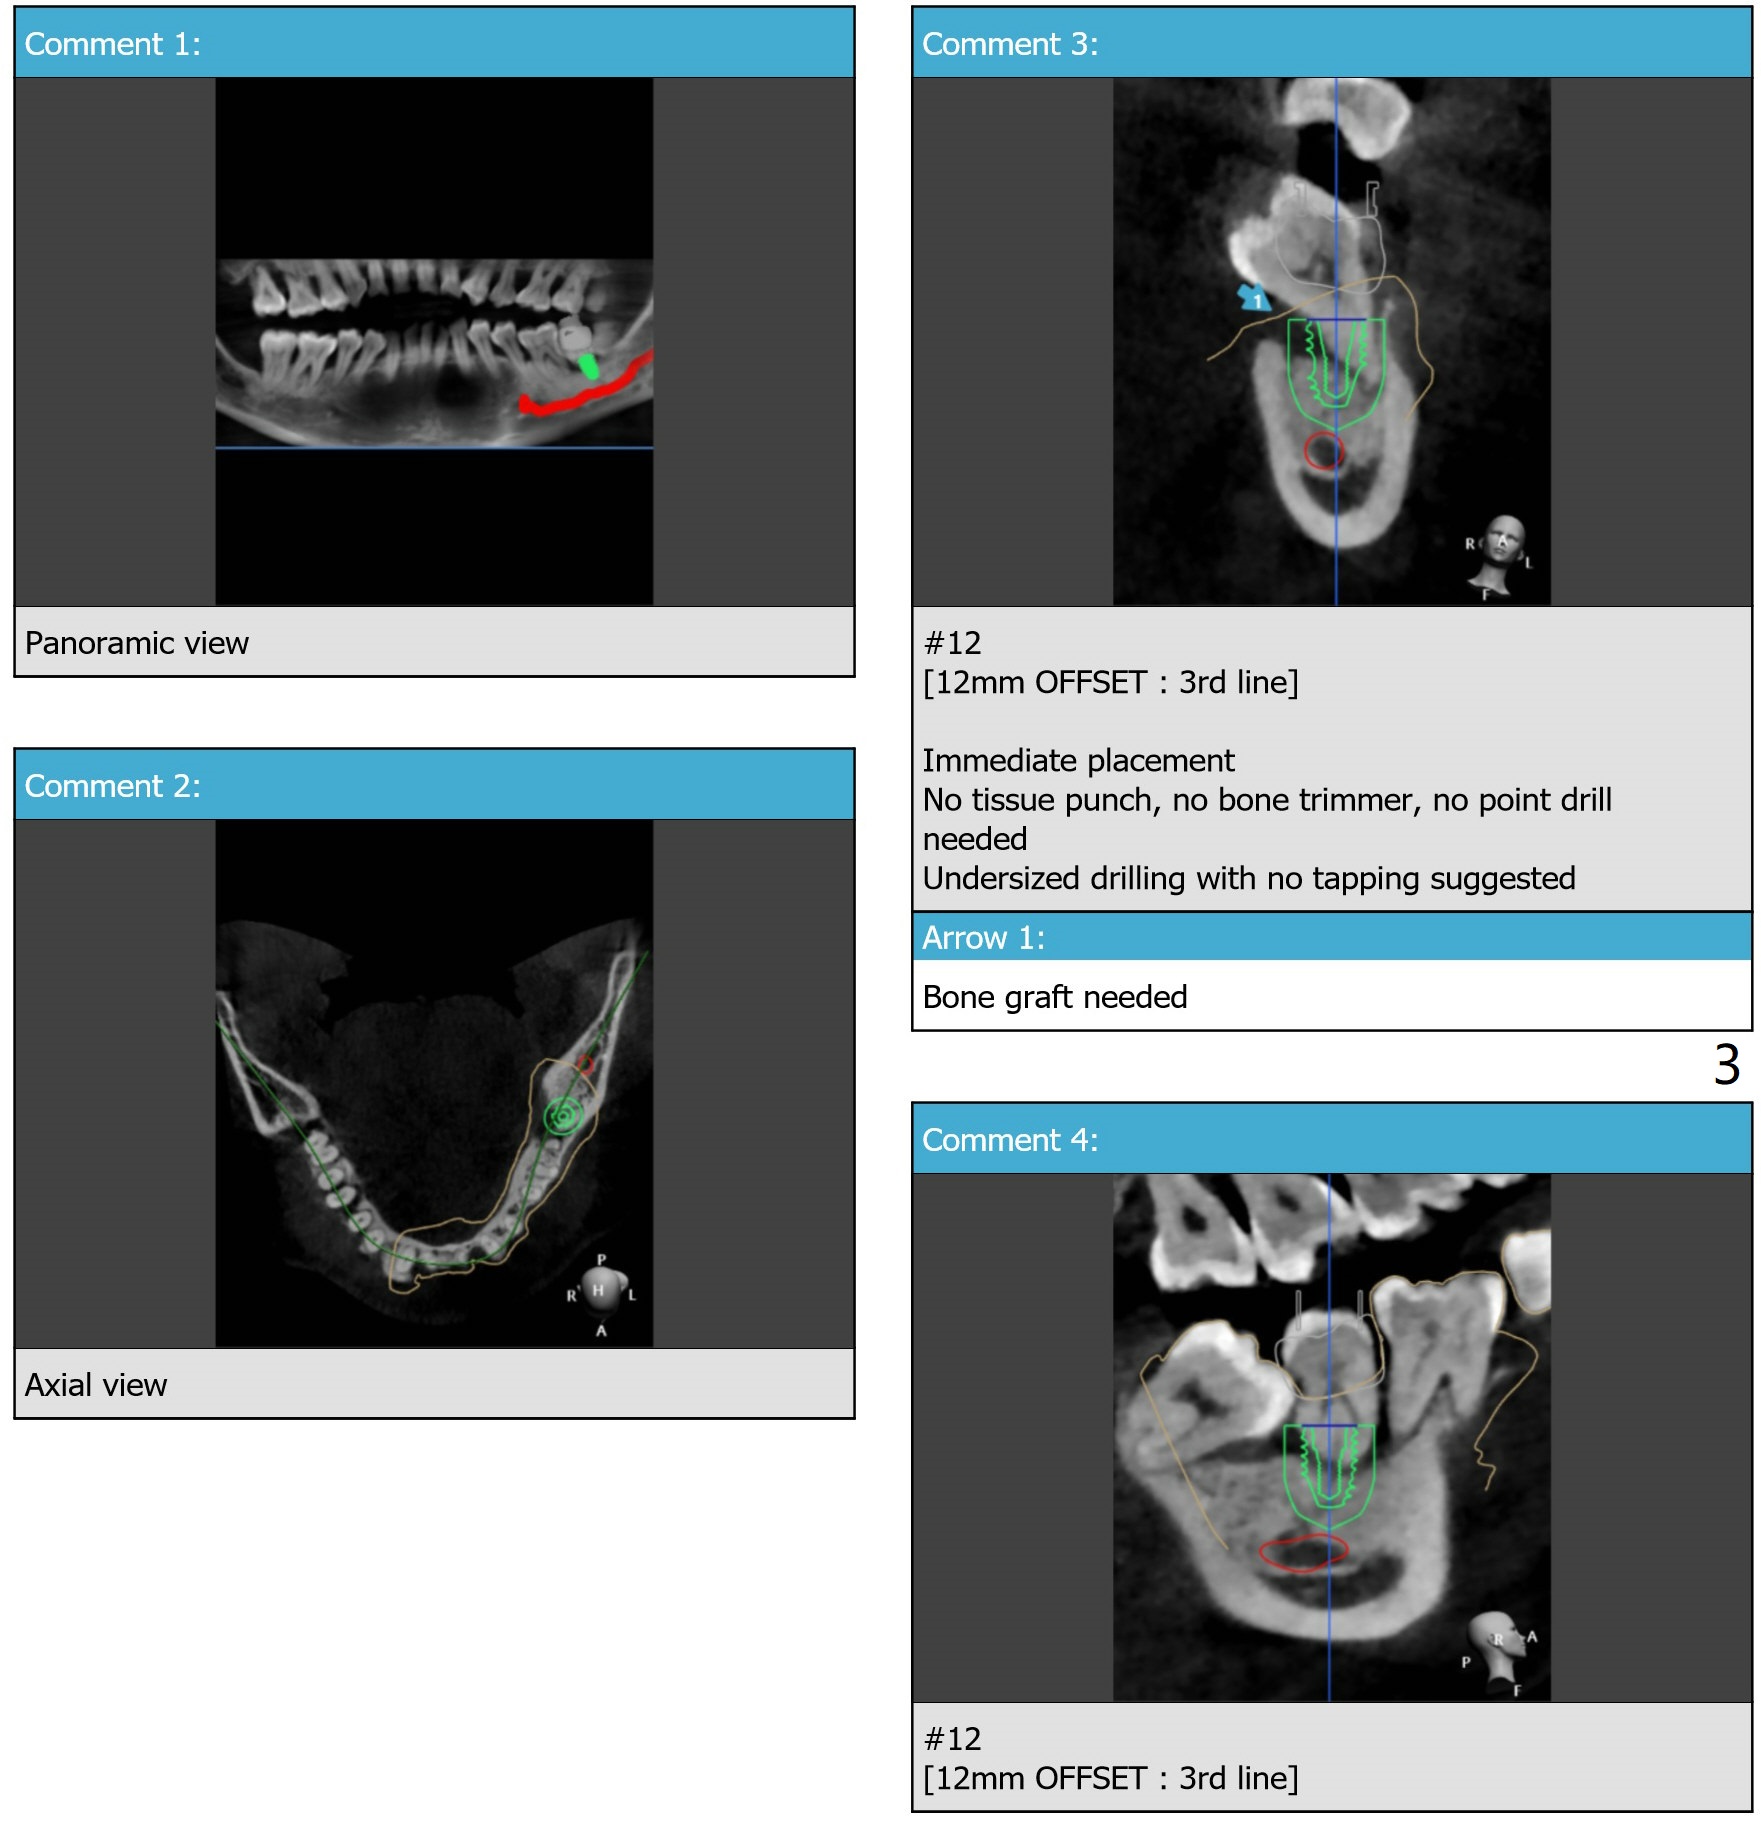

5x7.3 mm Implant with Sticky Bone   M

The tooth #17 will be extracted after guided surgery.

Return to Lower Molar Immediate Implant, Trajectory II

Xin Wei, DDS, PhD, MS 1st edition 09/09/2019, last revision 02/02/2020